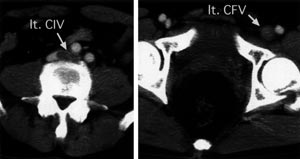

| Fig. 1 Preoperative enhanced computed tomography. lt.

CIV: left common iliac vein, lt.CFV: left common femoral vein |